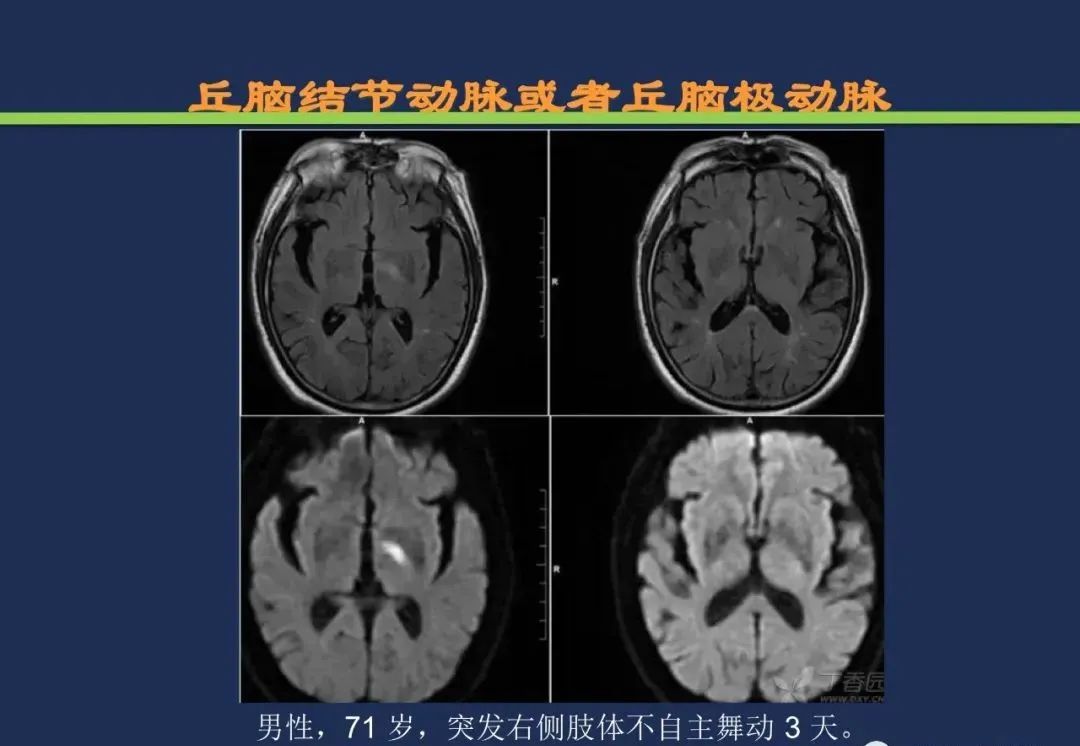

丘脑结节动脉